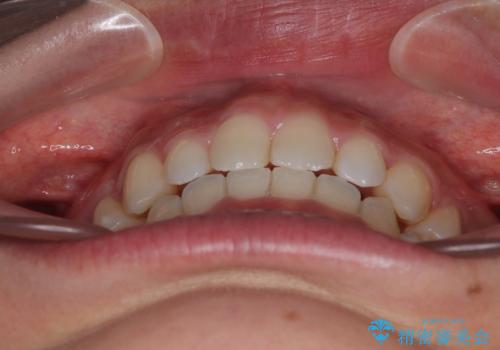

途中出産や育児があり、治療期間長くなってしまいましたが、ストレスなく唇が閉じられるような口元に仕上げることができました。